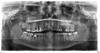

Doc Опубликовано 28 апреля, 2007 Поделиться Опубликовано 28 апреля, 2007 А не могли бы Вы назвать эту пару способов, чтобы хоть знать к чему стремиться. Насчет уколов все понятно, спасибо. Буду искать других специалистов. Главное - пройти каналы нормально, до верхушки, а потом грамотно их запломбировать. Второй вариант, учитывая разрежение в бифуркции (между двумя корнями), если это разрежение сфотографировать прицельно и оно там имеет серьезные причины, то можно сделать гемисекцию, это когда разрезают зуб между корней. Есть еще премоляризация, но это уже кружева, которые и обсуждать пока не стоит, глядя на один только снимок в интернете. Еще мне не нравится верхняя правая семерка и еще непонятно что за пятно над ней в области гайморовой. Судя по очень четким границам это просто наложилось что-то круглое, просто не люблю когда чего-то не понимаю. Ссылка на комментарий